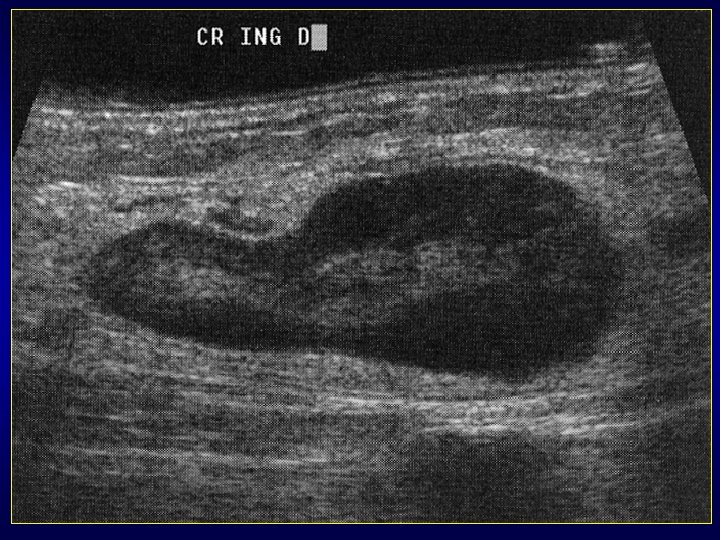

Lésion liquide ou solide? Lésion liquide quand: • Compressibilité sous la sonde+++ • Renforcement postérieur des échos • Le + svt anéchogène • Avasculaire • Collet avec raccordement à une articulation

Kystes mucoïdes atypiques • Entité polymorphe fréquente • Formations kystiques proches articulation avec 2 variétés: - les kystes synoviaux vrais entourés d’une mb synoviale (ex: de Baker) - les kystes mucoïdes (méniscaux, intraarticulaires, para-articulaires, intraneuraux, intra-artériels, intra-osseux)